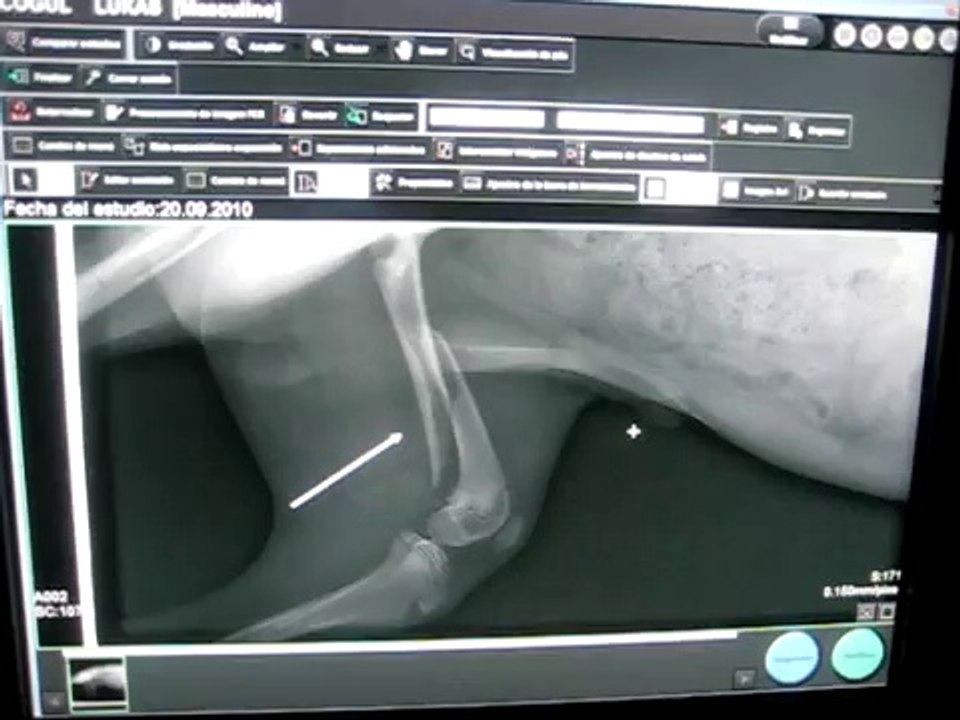

CIM Formación - Radiografía digital en veterinaria 0:56

CIM Formación - Radiografía digital en veterinaria